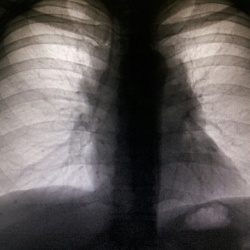

Женщина 1951 г р. 4 года назад прооперирована по поводу недостаточности митрального клапана. Сердце огромных размеров.. КТИ 80%,если правильно вычислил.